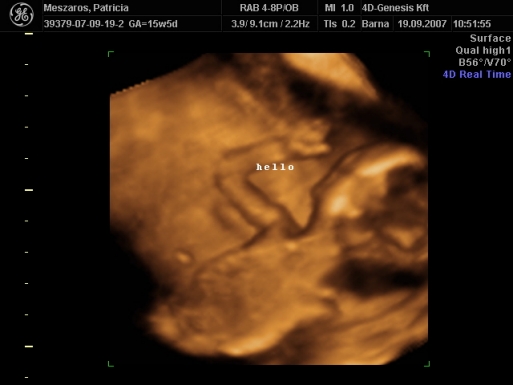

Üdv az újaknak! Itt valóban nagyon parás kismamák vannak, én az első 12 hetet végigparáztam, utána már csak mértékkel, de amióta mozog a bébi, meg láttam 4D-n, azóta oltári nyugodt vagyok...

Délután megyek a dokimhoz, terhesgondozásra, most kapok időpontot a következő UH-ra. Szerintem két hét múlva megyek, mert jövő héten sulihetem lesz, úgyhogy az kilőve. De most annyira nem is sürget a dolog, mivel a múlt héten volt a 4D.

Én is ajánlom mindenkinek a 4D-t, mi is nagyon jó helyet fogtunk ki, de mi vidéken, Szombathelyen voltunk, az van közel.

Egyébként mint megtudtam, ez a rendelő a Telki Magánkórház partnerintézete. Mondjuk elég luxus szinten mennek a dolgok, az biztos. De főleg az volt jó, hogy a szonográfus nő tök profi volt, és nagyon jól elmondott mindent, szinte minden részét láthattuk a kis kincsünknek, és még a nemét is megtudtuk kb. 9 perc után.

Szóval én nagyon meg voltam elégedve a szolgáltatással, egyébként 20 perces vizsgálat volt, szívhangot kihangosították, minden részét alaposan megnézték, kaptunk DVD-t, meg postán kapunk fényképeket. És ez volt 12.000 Ft.